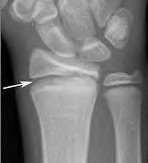

A 35-year-old woman reports wrist pain after a fall onto an outstretched hand. On exam, she has focal tenderness over the wrist snuffbox. A radiograph and CT image are shown in Figures A and B. What is the proper treatment of her injury?

Contrast enhanced MRA of the wrist is typically used to diagnose hypothenar hammer syndrome or other vascular abnormalities.